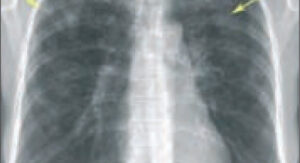

Эозинофильная пневмония (синдром Леффлера) — редкое заболевание у взрослых, при котором кровь и легочная ткань поражены эозинофилами. Они представляют собой серию гранулярных лейкоцитов, которые имеют двудольное ядро ​​и могут краснеть при воздействии специального вещества — эозина. Отсюда и название этого типа лейкоцитов. Выявить это заболевание можно только с помощью лабораторных исследований. В основном возрастной порог …